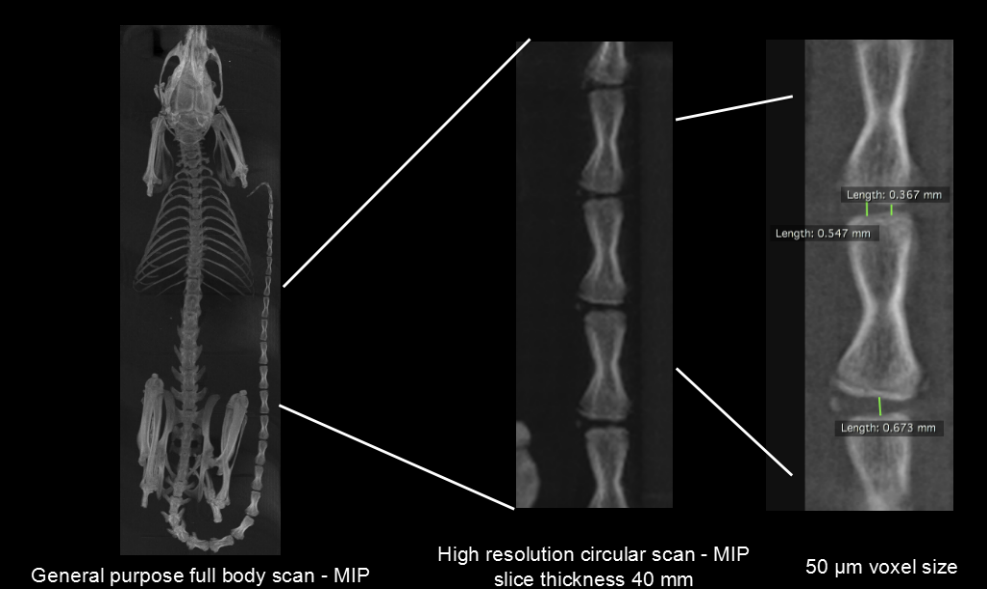

鼠的尾椎骨活體測量:高清晰度環(huán)形獲取,獲取時間:2min3s,ISRA重建,50μm voxel size。

尾椎骨測量.png

鼠的脊椎骨活體測量:高清晰度環(huán)形獲取,獲取時間:4min,F(xiàn)DK重建,50和20μm voxel size。

脊椎骨測量.png